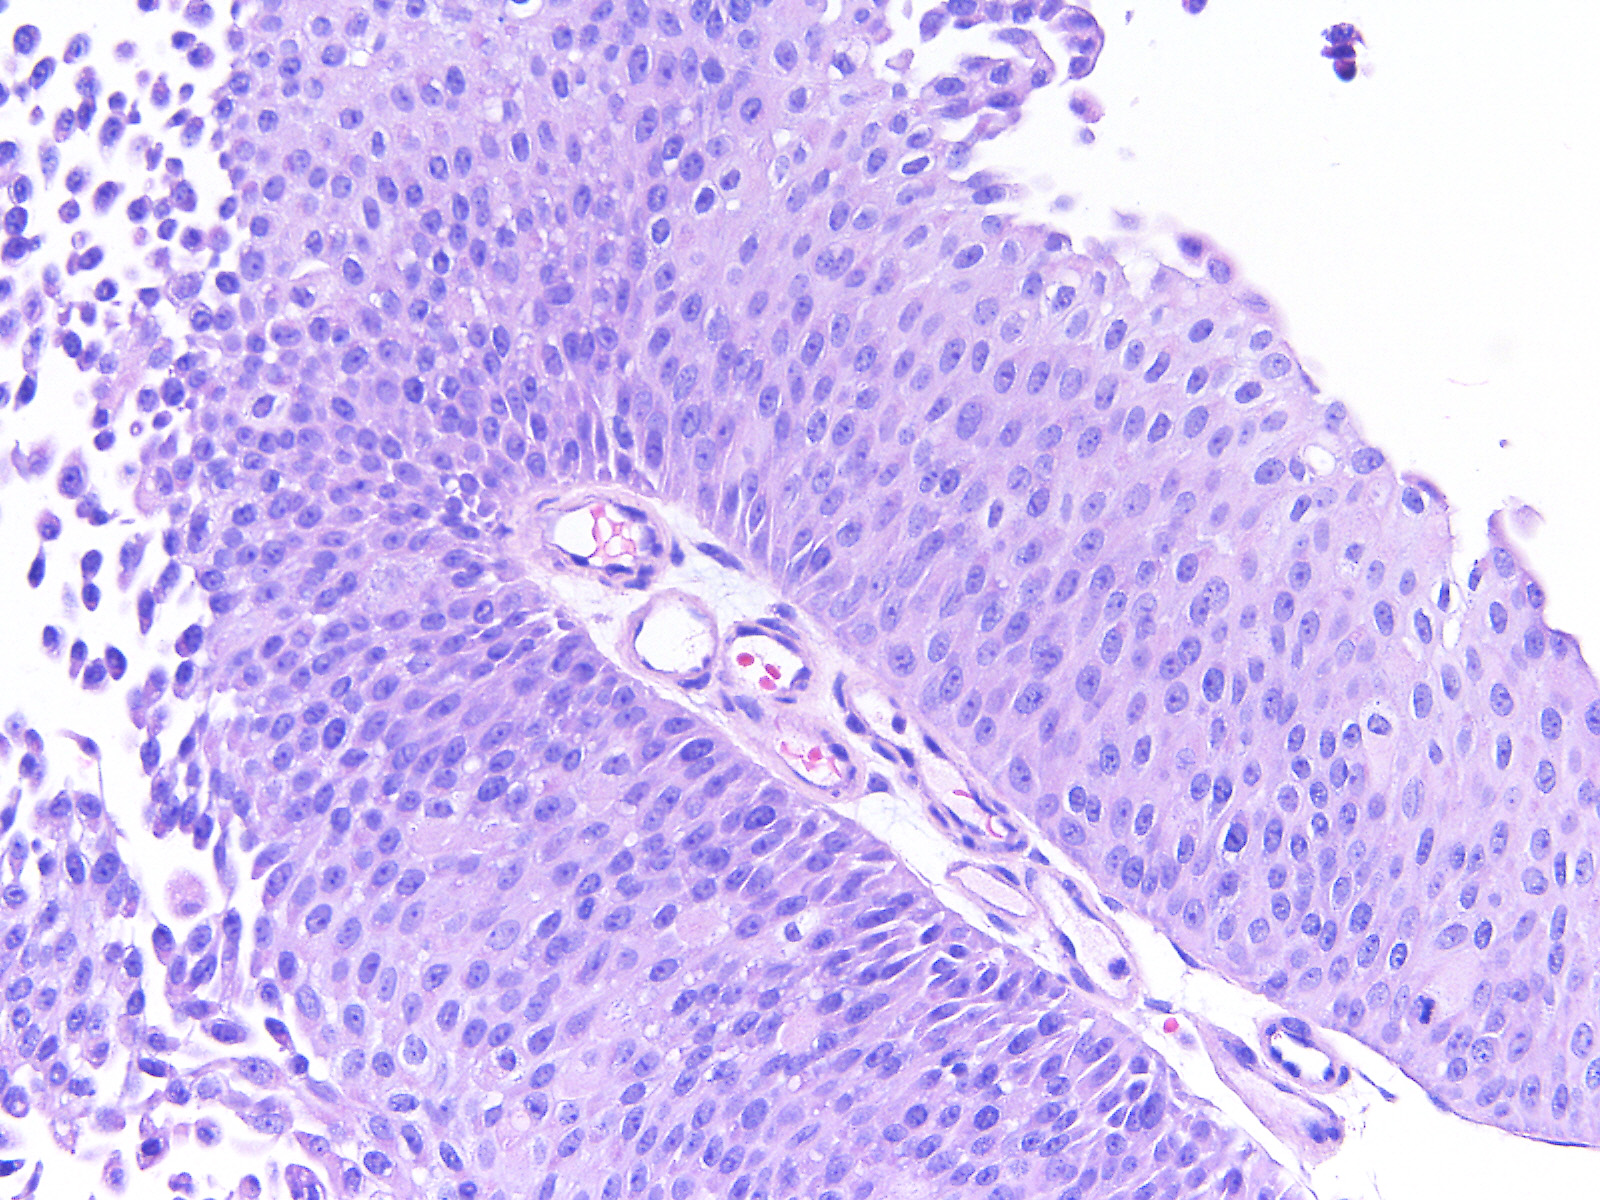

Bladder Papillary Lesions

Case ID: 559